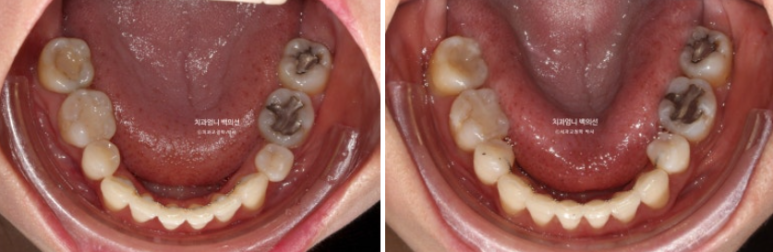

23년 8월 재교정치료를 위해 내원한 환자분입니다.

환자분은 어금니가 닿도록 끝까지 물면 아래턱이 뒤로 밀리는 증상때문에 재교정을 원했습니다.

또한 아래턱이 뒤로 밀리다보니 아래 앞니가 뒤로 너무 쑥 들어가보이는 부분도 개선을 원하셨습니다.

23.08

블랙트라이앵글과 중심선 불일치가 보입니다.

잇몸이 얇은편이라 작은어금니 부분에 잇몸퇴축도 보입니다.

얼굴에 비해서 위 앞니 중심선이 좌측으로 돌아간 상태인데

원인은 좌우 치아 갯수 차이에 있었습니다.

오래 전 했던 발치교정으로 작은어금니 4개가 없는 상태인데 좌측 첫번째 큰어금니 1개가 추가로 더 없습니다.

상악 좌측에만 치아갯수가 2개나 없는 것 입니다.